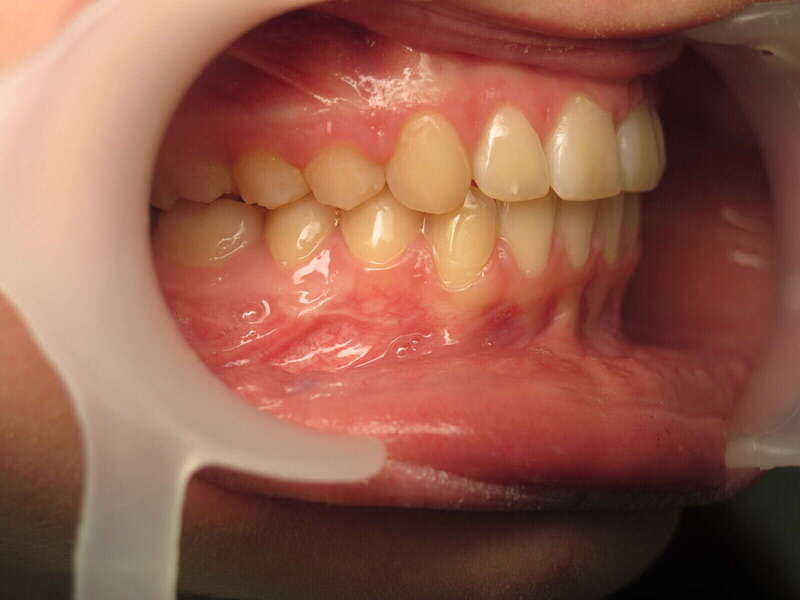

Cas n°1 traité par aligneurs - adolescent

Ce cas d’une adolescente illustre la correction d'une Classe II avec supraclusion par aligneurs. La stratégie thérapeutique a reposé sur une distalisation séquentielle de l'arcade supérieure. Ce mouvement précis a permis de reculer les dents maxillaires étape par étape pour annuler le surplomb (overjet) sans extractions.

• Correction fonctionnelle : Retour à un engrènement de Classe I stable et correction du recouvrement vertical.

• Esthétique restaurée : Harmonisation globale du sourire et du profil.

• Approche moderne : Un traitement discret, confortable et hautement prévisible.

Le résultat final montre une occlusion saine et un sourire parfaitement aligné, garantissant une santé dentaire et articulaire optimale pour l'avenir.